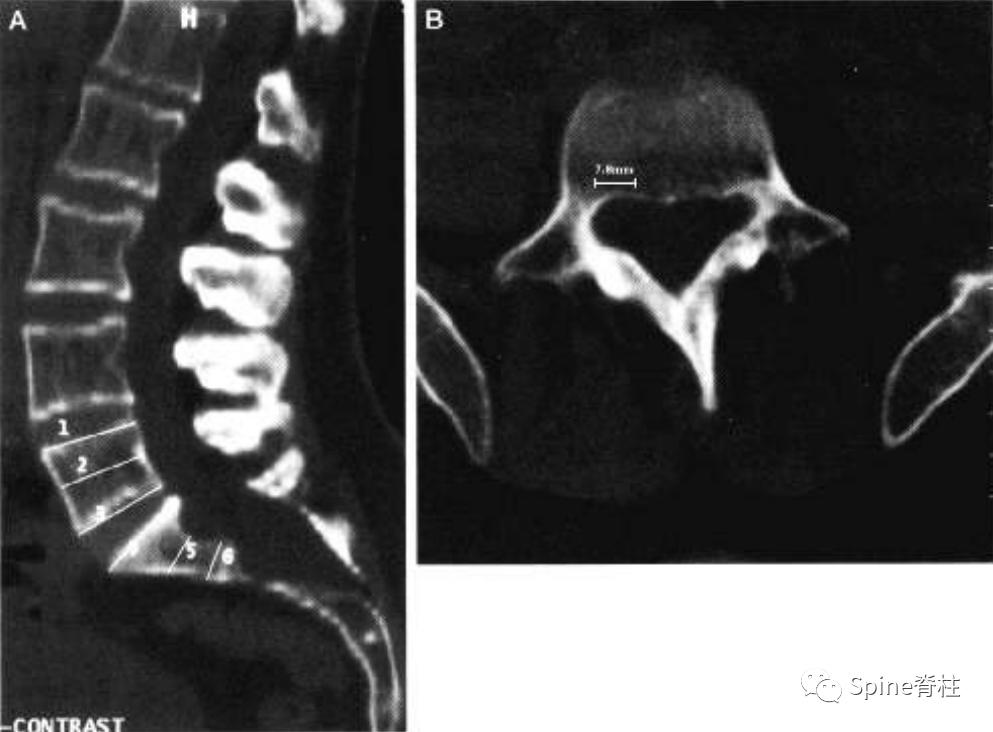

测量L5处的最大神经根袖直径 (nerve root sleeve diameter) 。请注意,神经根袖的直径右侧为7.3 mm,左侧为4.5 mm。因此,L5神经根袖的最大值为7.3 mm,这符合次要标准之一。只有当最大值超过6.5 mm时,才满足L5神经根袖直径的次要标准。

一位马凡综合征伴硬膜扩张患者的CT图像。a为正中矢状位重建,可见S2的椎管宽度大于L4。S1扇形缺损值为4.2mm。b为L5水平的横断面提示一个神经根袖的直接为6.6mm。因此,这个患者满足一个主要标准和两个次要标准。